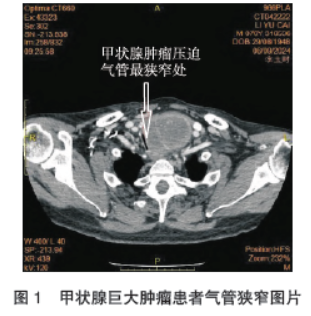

颈部软组织三维重建提示:甲状腺左叶见软组织团块,密度不均,大小为4.9 cm×5.1 cm×5.9 cm,向下延伸至胸廓入口,气管上段约T1-T2 椎体水平局部受压狭窄,吸气相最狭窄处短径约0.26 cm,呼气相最狭窄处短径约0.38 cm,狭窄范围约为2.18 cm,狭窄处距气管隆突9.80 cm,狭窄处距声门约为7.40 cm(图1)。